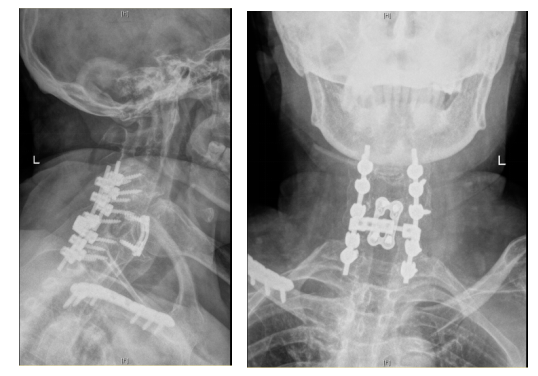

手术室、麻醉科等相关科室高效联动,医护密切配合,小心翼翼地协助患者调整颈部角度,多位资深麻醉医生紧密配合成功插管,在保障患者安全、避免脊髓二次损伤的前提下,尽可能扩大手术视野。手术中,曾浩带领手术团队凭借精湛的医术和丰富的临床经验,在狭窄的操作空间内精准操作、成功完成手术,并最大限度地保护了受损的脊髓神经,为患者的康复争取了希望。

术后复查CT影像结果

手术成功只是第一步,术后的护理与康复同样至关重要。在许湘红护士长带领的护理团队专业照护下,张阿姨恢复情况远超预期:从术后四肢毫无知觉,到逐渐能活动手指、抬动手臂,再到可以自主翻身、坐起,最终肢体肌力恢复到4级,顺利出院。